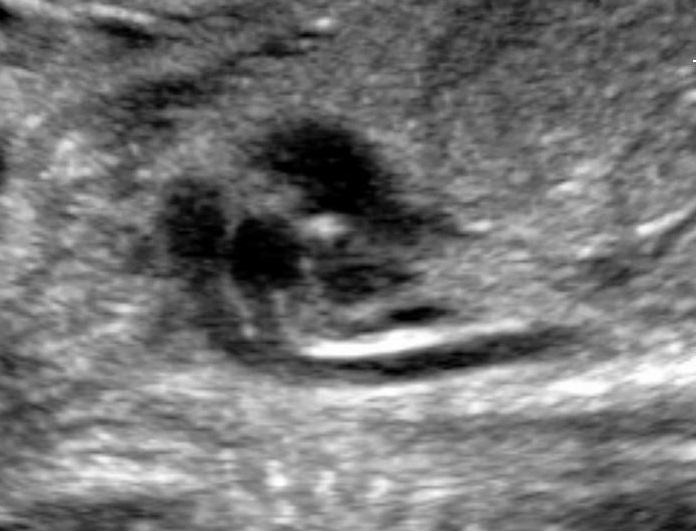

Diagnosing Polyhydramnios

The gestational week does not influence the diagnosis of polyhydramnios. The size of the uterus could be suggesting of this condition, however the diagnosis should be made during ultrasound examination. There are two common ways to estimate the volume of the amniotic fluid:

- Single Deepest Pocket (SDP). A vertical measurement in the deepest amniotic fluid pocket. Values below 2 cm indicate oligohydramnios, values over 8 cm indicate polyhydramnios (8-11: mild, 12-15: moderate, > 16: severe). In multiple gestation, a range of 3–8 cm is defined as normal. Another technique is the

- Amniotic Fluid Index (AFI). This is the sum of vertical measurements of all four quadrants (polyhydramnios usually >24).